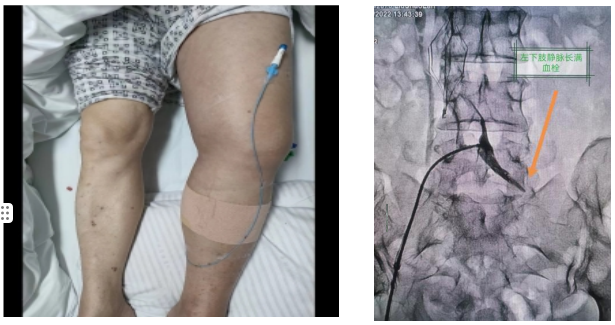

介入治疗室,医生首先经健侧股静脉穿刺置入下腔静脉滤器,再而采用超声引导下穿刺病变侧腘静脉建立入路,经腘静脉入路利用负压机械血栓抽吸系统反复抽吸髂静脉至股静脉段血栓,大幅减少新鲜血栓负荷,并配合导管内局部溶栓治疗快速消除血栓。造影证实存在髂静脉显著受压,医生立即行递增式球囊扩张,该技术既能快速清除血栓负荷使静脉全程复流,最大限度保护深静脉瓣膜功能,又能同时处理合并髂静脉压迫综合征,预防血栓复发,具有微创性,疗效好、见效快,定位准确,可重复性强的特点。此患者经心血管内科介入治疗后,左下肢肿胀明显消退,肢体疼痛缓解,快速恢复行走活动能力。